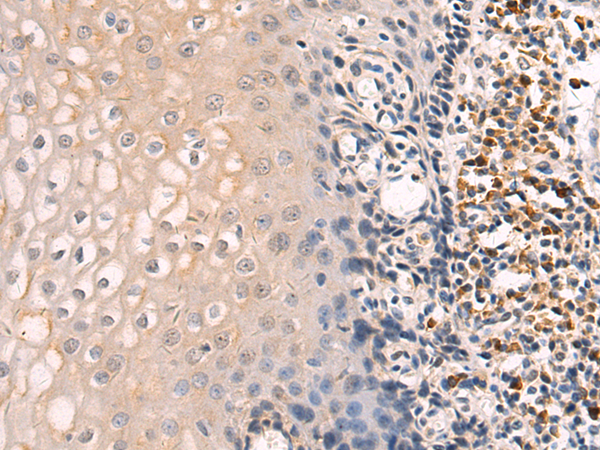

分类: 科研抗体货号: P07775别名: MDC15应用: WB,IHC反应种属: Human, Mouse, Rat